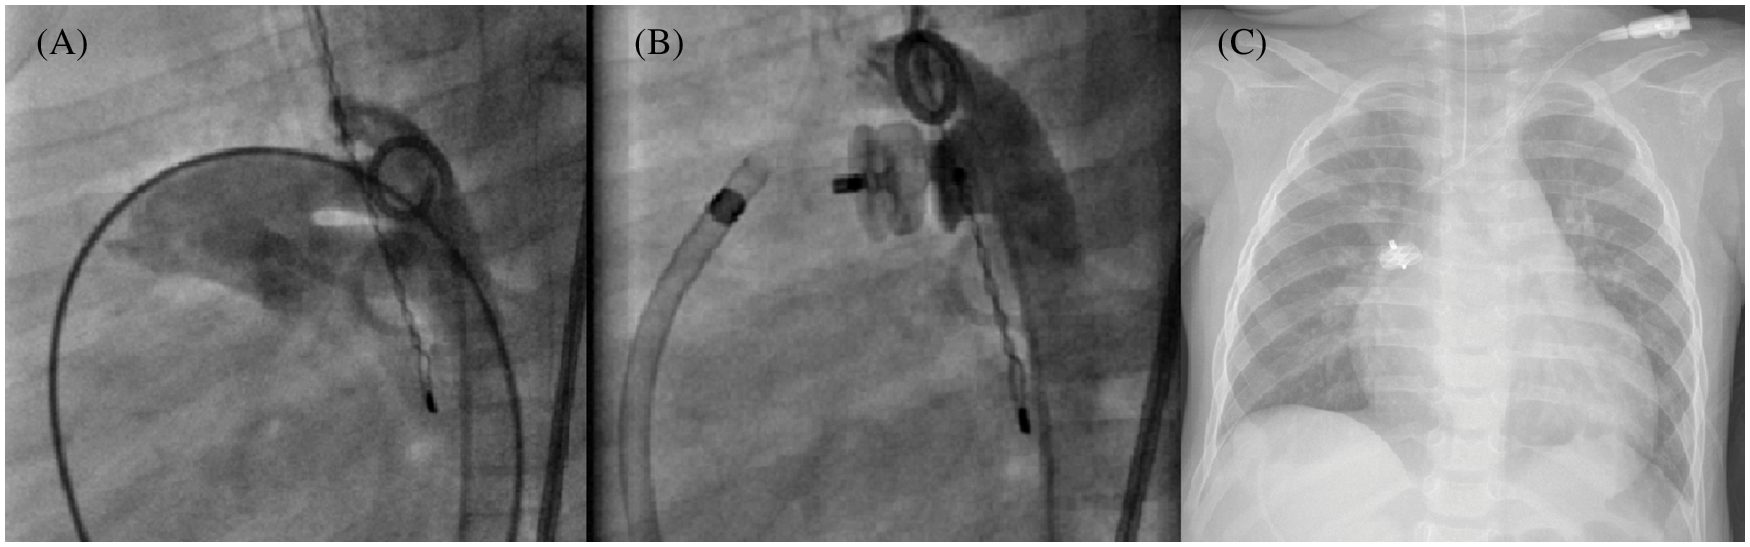

In all, there were a total of 4 device embolization, always observed within the first 24 h (Fig. 5), 2 of which were recovered by snaring technique in the catheter laboratory, and 2 by surgical removal.

Figure 5: Early embolization of a 10 mm AVP II after PDA closure. Multiple angiograms, lateral view, and chest X-ray. (A): Aorta with a 7 mm tubular PDA; (B): Post device release final result; (C): Device embolization into the right pulmonary artery

Additional surgical procedures were performed in 2 patients presenting delayed severe LPA stenosis. The latter were documented 2 weeks after PDA closure in a 3.2 kg baby (10 mm AVP II) and 8 weeks after the procedure in another infant weighing 4.9 kg (10 mm PDA, 14 mm AVP II). This patient presented with a device “attraction” of the descending aorta and severe plication of the LPA. The last MAE involved a 3.6 kg infant already on inotropic support at the entrance to the catheterization room who presented a cardiac arrest during the first aortography. He was successfully resuscitated. There was no EKG modification, with unremarkable immediate coronary angiogram. PDA closure was successfully achieved using a 6 mm AVP II. Three other mild LPA stenosis did not require treatment, with uneventful follow-ups. There was no haemolysis, severe bleeding, cardiac arrhythmia, or late embolization.